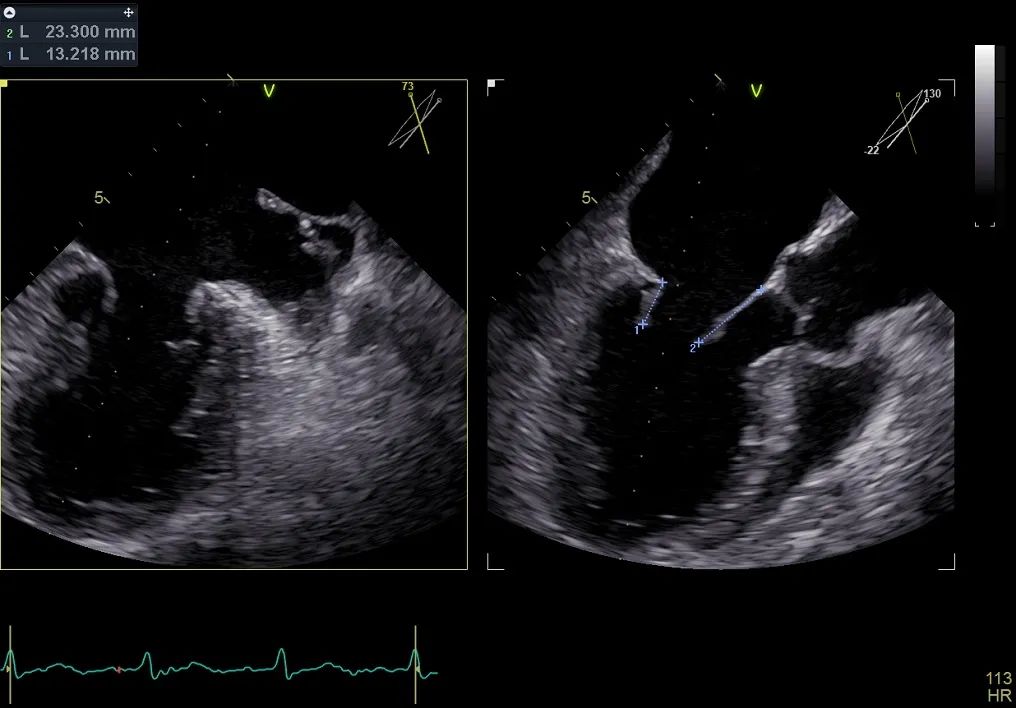

术前行经食道超声评估

原发性二尖瓣反流,反流程度4+;二尖瓣瓣口面积4.15cm²,平均跨瓣压差5mmHg,二尖瓣前叶(A2)长度23.35mm,二尖瓣后叶长度(P2)长度13.2mm;左室射血分数67%。患者手术风险高,操作难度大,经心脏瓣膜团队多次充分讨论评估后,决定行经导管二尖瓣缘对缘修复治疗。

术前MDT策略:从解剖结构来看二尖瓣后叶脱垂伴连枷涉及整个2区,累及3区和1区,宽度15mm左右,且连枷高度甩起高度有7-8mm,可见长达10.4mm的飘样回声,术前策略预计使用两个二尖瓣夹,较小的二尖瓣口面积和较高平均跨瓣压差,是一次高难度的挑战。